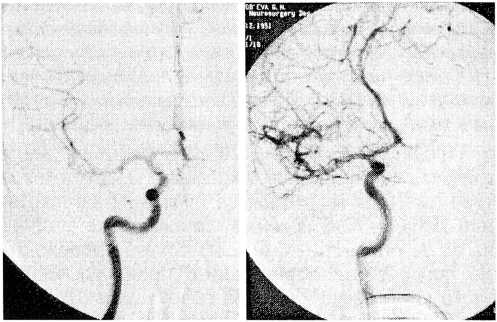

Интраоперационно принято решение о проведении реканализации обтурированных сегментов церебральных сосудов. Проведена замена интродъюсера на IVA 6F. Манипуляционный катетер ENVOY 6F проведен в левую ВСА субкраниально, по нему с использованием микропроводника проведен микрокатетер. Начата реканализация левой ВСА, ПМА и средней мозговой артерии (СМА) с использованием сочетания гидравлического, механического (микропроводником и устройством «Goose Neck» (Amplatz Snare)) методов и тромболитической терапии (стрептокиназа 1500 000 ЕД селективно в проксимальную часть тромба). В ходе манипуляции удалось достигнуть стабильного восстановления проходимости левой ВСА до уровня С1 сегмента, отмечено контрастирование левой глазничной артерии, задней соединительной артерии и сосудов вертебробазилярного бассейна из левой ВСА. Достигнуть стабильной реканализации левой ПМА А1, левой СМА не удалось, при суперселективной ангиографии через микрокатетер в просвете левой ПМА А1 и СМА отмечались дефекты наполнения просвета сосуда, обусловленные тромботическими массами (рис. 6-9).

Рис. 6-7. Больная В., дигитальная суперселективная ангиограмма левой СМА (выполнена через микрокатетер).

Ствол СМА (M1сегмент) визуализируется фрагментарно, заполнен тромботическими массами

Рис. 8-9. Больная В., дигитальная субтракционная ангиограмма левой ВСА (косая проекция) (результат тромболизиса и реканализации).

Достигнуто восстановление проходимости левой ВСА до супраклиноидного отдела